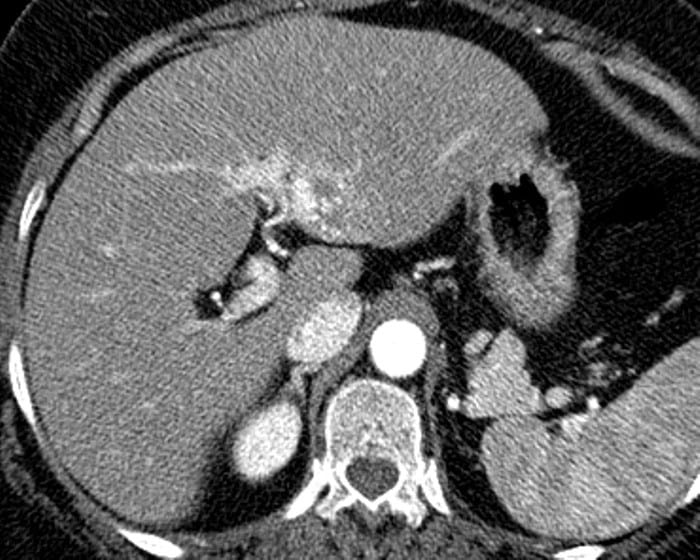

Ung thư đường mật

» Thông tin: Nữ giới – 56 tuổi.

» Lâm sàng: Viêm gan C.